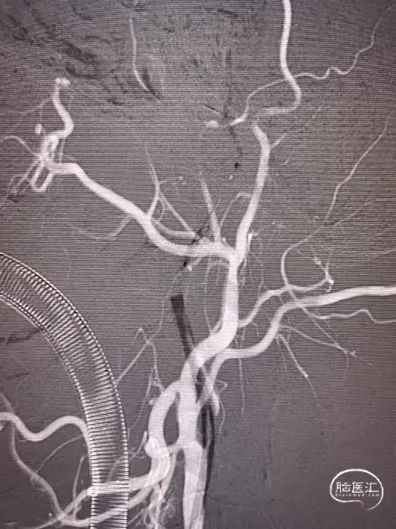

造影可见:颈内动脉起始部闭塞。

术中使用90cm NeuronMax、 125cm多功能管及泥鳅导丝,但NeuronMax无法通过闭塞段,远端可见继发长节段血栓。

随后选择Sterling3×30 8atm的球囊通过血管进行球囊扩张。选用中间导管进行抽吸,再通过微导管、微导丝进入大脑中动脉,进行持续抽吸,抽吸出长节段血栓。随后近端可见充盈缺损,将保护伞回收,回收血栓后重新植入保护伞。随后进行球囊扩张及支架成型。

术中脑血管造影:

随后串联病变越过起始部。